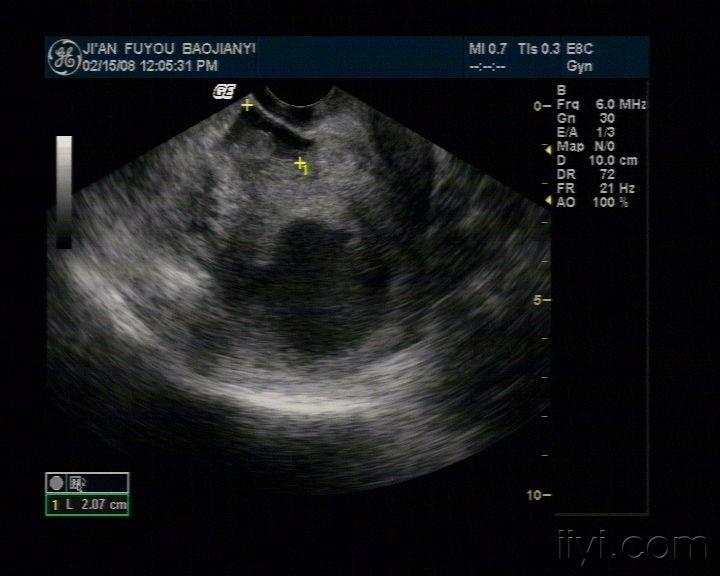

右侧附件区见混合回声光团,形态不规则,边界不清,内见类孕囊结构,大小47*27mm,见胎儿及原始心血管搏动,头臀长30mm。子宫直肠窝见液性暗区,最大厚径为21mm。

右侧附件区见混合回声光团,形态不规则,边界不清,内见类孕囊结构,大小47*27mm,见胎儿及原始心血管搏动,头臀长30mm。子宫直肠窝见液性暗区,最大厚径为21mm。